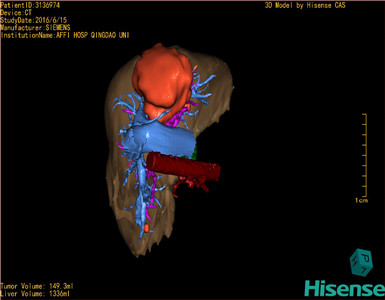

将0.625mm双源薄层CT资料的静脉期和动脉期Dicom格式文件导入海信CAS系统。

通过调节窗宽窗位调整CT序号,对肿瘤,肝实质,胆囊,下腔静脉,肿瘤,肝动脉、门静脉及肝静脉等进行三维重建;系统自动计算肿瘤体积和肝脏体积。

模拟手术操作,自动计算切除肿瘤体积。肝脏体积为1336ml,肿瘤体积为149.3ml,肿瘤体积为肝脏体积的11.2%,通过比对50-60岁正常肝脏体积为1330.41±329.13 ml,通过术前模拟手术,精准判断切除后剩余肝脏体积能耐受,避免肝衰竭发生。

术前手术方案的规划。

术前三维重建:重建图片